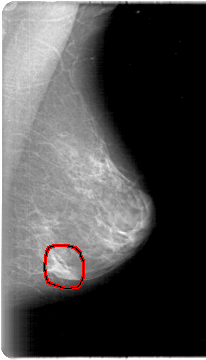

D_4024_1.LEFT_CC

LEFT_CC LINES 5386 PIXELS_PER_LINE 3046 BITS_PER_PIXEL 12 RESOLUTION 43.5 OVERLAY

FILE: D_4024_1.LEFT_CC.OVERLAY

TOTAL_ABNORMALITIES 1

ABNORMALITY 1

LESION_TYPE MASS SHAPE LOBULATED MARGINS CIRCUMSCRIBED

ASSESSMENT 0

SUBTLETY 3

PATHOLOGY BENIGN

TOTAL_OUTLINES 1

BOUNDARY